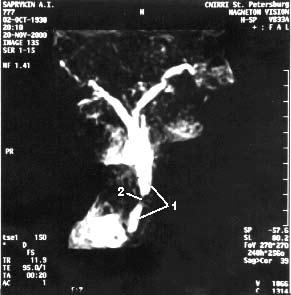

Магнитно‑резонансная томография (МРТ), по данным большинства исследователей, не имеет существенных преимуществ перед УЗИ и КТ в диагностике заболеваний поджелудочной железы. Кроме того, МРТ отличается более высокой стоимостью. В последние годы появился новый неинвазивный метод – магнитно‑резонансная холангиопанкреатография который позволяет визуализировать желчные и панкреатические протоки без инвазивных вмешательств и введения контрастных веществ. Это исследование осуществимо у всех больных, не дает осложнений и позволяет получить такую же информацию, как и при одновременном применении КТ, ангиографии (АГ) и эндоскопическая ретроградная холангиопанкеатография (ЭРХПГ) (рис. 101. а, б).

Рис. 101. Магнитнорезонансная холангиопанкреатикография. Рак головки ПЖ. А – отмечается дефект наполнения (2) в панкреатической части холедоха (1) на протяжении 1 см. Опухоль диаметром 1,5 см была выявлена только интраоперационно. Б – отмечается дефект (3) в месте слияния общего желчного (1) и панкреатического (2) протоков. Имеется супрастенотическое расширение протоков. Опухоль диаметром 3 см была выявлена при УЗИ, КТ и интраоперационно